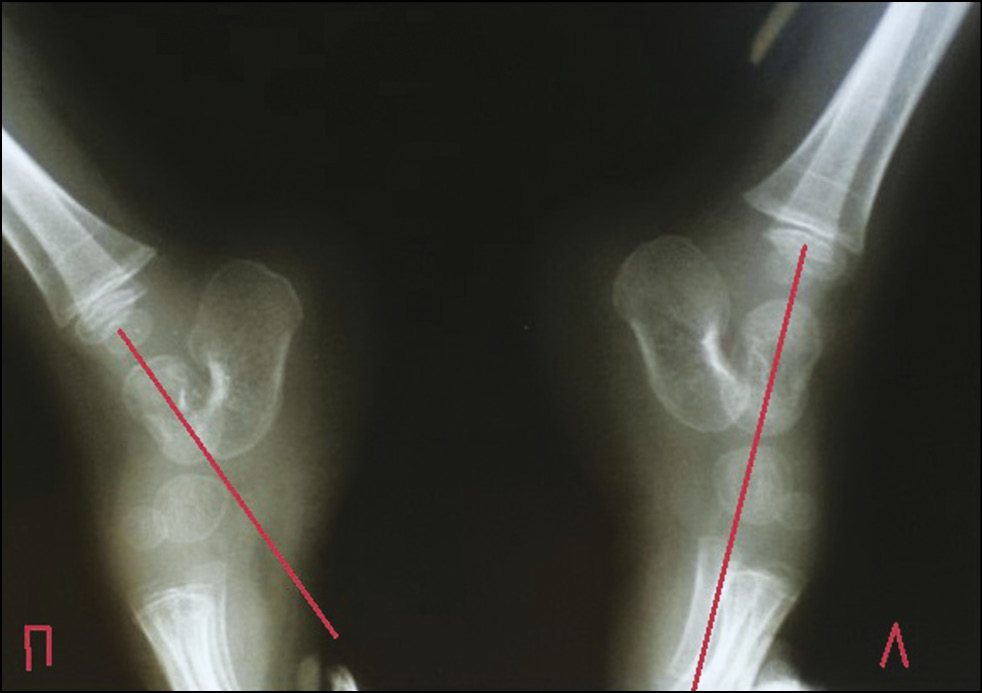

Рис. 2. Пациент П., 17 лет. Прямая и боковая рентгенограмма стопы с нагрузкой. Вертикальное положение таранной кости с двух сторон

Fig. 2. Patient P., 17 years old. Direct and lateral radiographs of the feet with stress. The vertical position of the talus from 2 sides